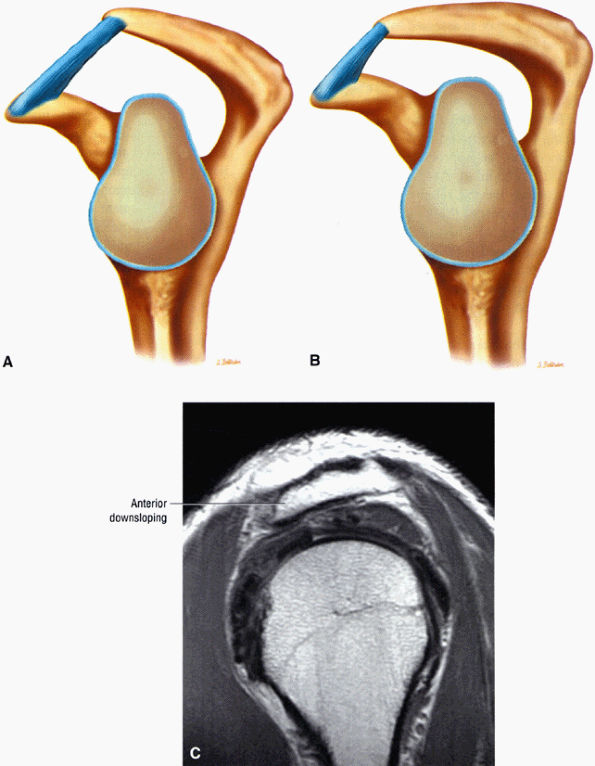

The acromion is classified into several types according to its morphology:

Type 1 (a flat or straight undersurface with a high angle of inclination)

Type 2 (a curved arc and decreased angle of inclination)

Type 3 (hooked anteriorly with a decreased angle of inclination)

Type 4 (upward convexity of the inferior surface) (see also the discussion of the etiology of shoulder impingement syndrome)